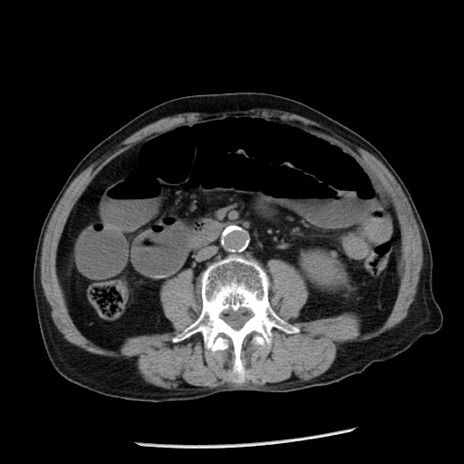

症例26(横断像)

【症例】80歳代男性

【主訴】嘔吐

【現病歴】昨晩2回嘔吐あり、今朝になっても嘔吐あり。来院。

【既往歴】胃潰瘍

【身体所見】意識清明、BT 37.6℃、BP 166/95mmHg、HR 100bpm、SpO2 97%、腹部:平坦・軟、腸蠕動音聴取良好、圧痛なし。

【データ】WBC 21900、CRP 1.46